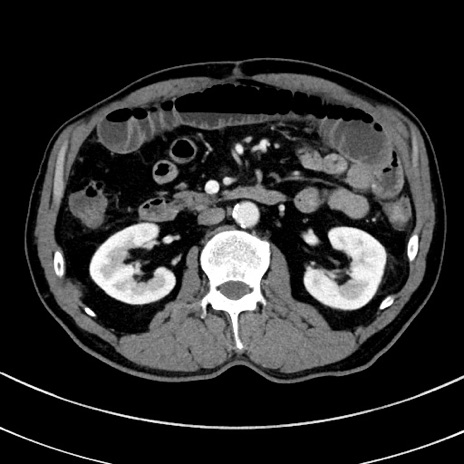

症例8(横断像)

【症例】 60歳代男性

【主訴】 黒色吐物

【現病歴】 4日前から嘔気自覚、2日前の朝食後にも嘔気あり、自分で手で嘔吐反射起こし嘔吐したところ血が混ざっていたため受診。

【既往歴】 5年前汎発性腹膜炎を伴う急性虫垂炎で手術、高血圧、前立腺肥大症、高脂血症

【身体所見】 腹部正中に手術癩痕あり 腹部平坦・軟圧痛なし膨満感あり

【データ】WBC 8400、CRP 4.54